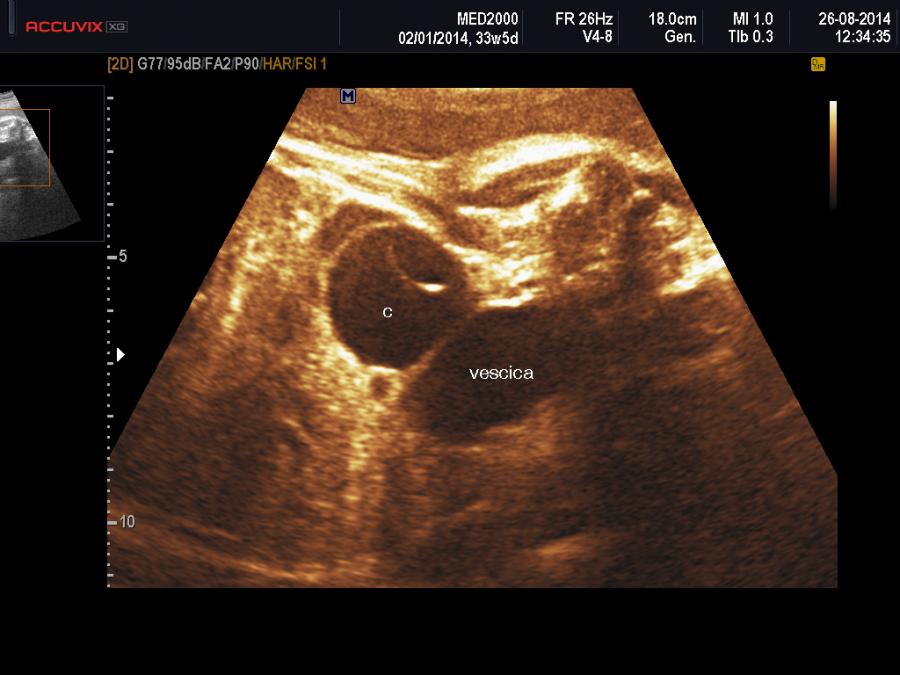

Una cisti ovarica fetale si manifesta comunemente come una Cisti Uniloculare a parete sottile localizzata superiormente e parasagittalmente alla vescica; occasionalmente può essere visualizzata al suo interno una cisti figlia aspetto questo patognomonico di cisti ovarica. L'aspetto può essere anche quello di una cisti complessa e in caso di emorragie endocistiche o di torsione possono assumere l'aspetto di Cisti Uniloculari Solide; in tali casi possono presentarsi con dei setti, con dei livelli o con echi interni mobili (Trinh TW  et al. 2015). Meno frequente è la presenza di cisti bilaterali.

Importanti per la diagnosi sono due elementi: 1) sesso femminile, 2) differenziazione dalla vescica urinaria: tale distinzione è agevole considerando che è possibile evidenziare, con l'ausilio del color-doppler, le due arterie ombelicali che decorrono lateralmente alla vescica.